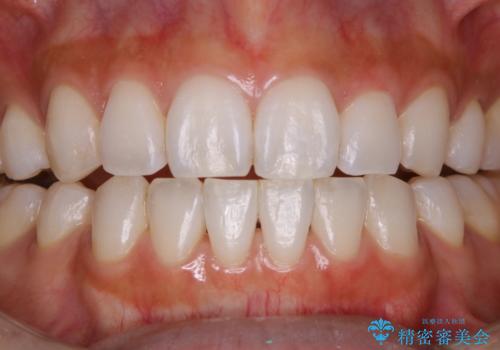

PMTCでスムーズにデンタルフロスが通るように

- フロスが以前よりも通りずらくなり、クリーニングしてほしいとのことでした。歯科医院でのクリーニングは3年ぶりとのことです。PMTC60分コースを行いました。

歯科医院で行なわれる専門家による徹底した歯面清掃をPMTC(Professional Mechanical Tooth Cleaning)といいます。専用の機器とフッ化物入り研磨剤を使用して、歯みがきで落とせない歯石や磨き残したプラークを中心に総ての歯面の清掃と研磨を行ない、齲蝕や歯周病になりにくい環境を整えます。

歯石が溜まると、歯と歯の間が埋め尽くされてしまい、デンタルフロスが通りずらくなったり、通せなくなります。